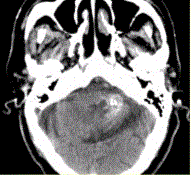

问题 男性,80岁,左耳听力下降伴头晕半年。头CT显示如下图。 诊断应为(提示进一步MR检查,病变显示如下图。)

选项 A.钙化灶 B.急性出血 C.动静脉畸形 D.海绵状血管瘤 E.胶质瘤 F.发育性静脉畸形 G.脑囊虫

答案 D